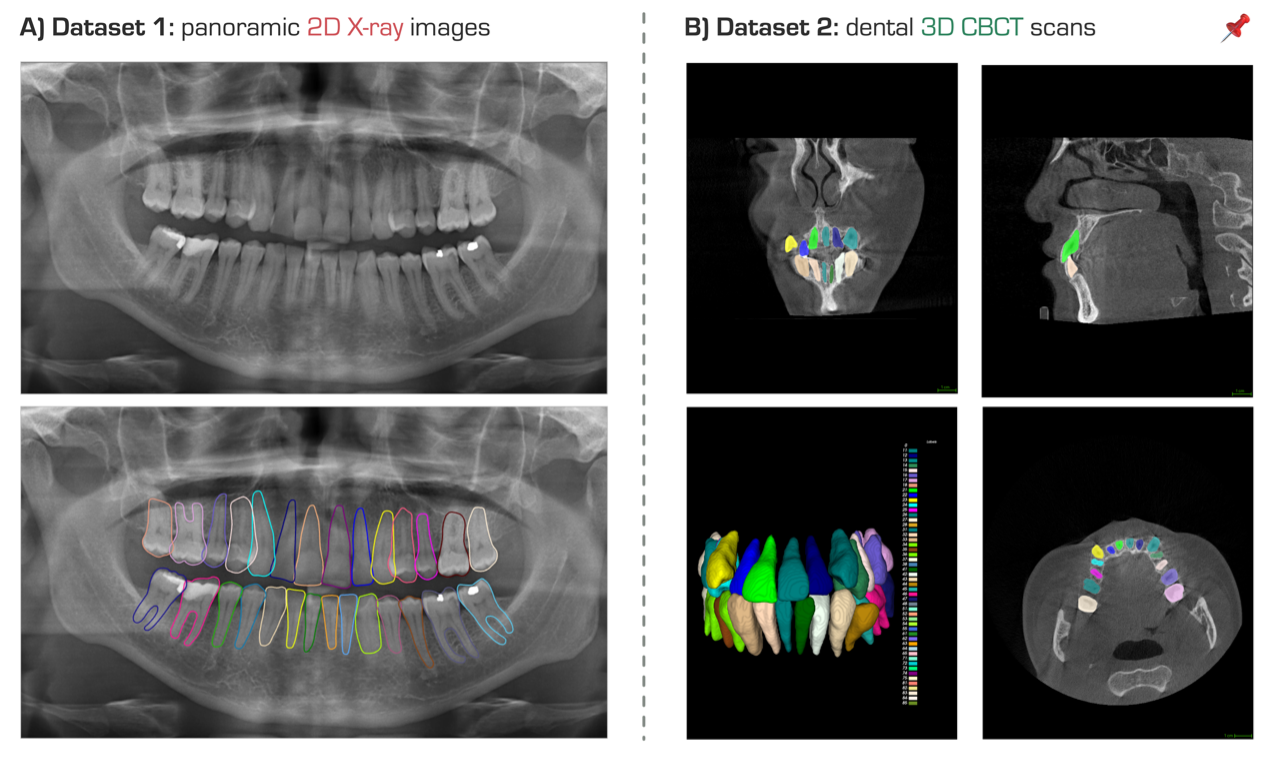

计算机辅助诊断工具在现代牙科中受到越来越多的关注,特别是用于治疗计划或预后评估。其中,2D全景X射线图像和3D牙科锥束计算机断层扫描(CBCT)是临床中广泛用于正畸和牙髓学的图像模态。然而,从全景X射线图像或CBCT扫描中定位识别牙齿,并进一步分割牙齿仍然是一件费时费力的工作,这限制了深度学习算法在牙齿实例分割和牙科疾病分析的发展。作为一种潜在的替代方案,半监督学习可以从未标注的数据中探索有用的信息。

STS MICCAI 2024挑战赛,致力于开发高效的半监督学习方法,从全景X射线图像或CBCT扫描中自动地分割不同的牙齿实例。通过参加该挑战赛,大家有机会获得以下丰厚的奖励:

STS 2024挑战赛提供了来自真实临床环境的多中心、全年龄段、标注最精细的牙科数据。具体来说,我们提供了两个任务和数据集:1)2D的全景X射线图像牙齿实例分割和2)3D的牙科CBCT图像牙齿实例分割。所有数据均经过伦理批准并匿名处理,确保了隐私和伦理标准的符合。下面是对挑战赛两个不同任务对应的数据集的详细划分信息:

任务1

全景X射线图像牙齿实例分割,jpg格式,共2450例:

任务2

牙科CBCT影像牙齿实例分割,nii.gz格式,共400例: